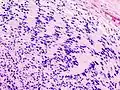

Микроскопический вид типичной нейробластомы с образованием розеток

Гистопатологический образец нейробластомы с розетками Гомера Райта, окраска гематоксилин-эозин